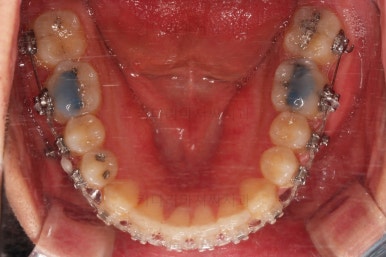

초진 시 입안의 모습입니다.

앞니가 약간 삐뚠 것 말고는 큰 문제는 없어보이네요.

장치를 부착했습니다.

이번 부산연제구교정 환자분이 선택한 장치는 엠파워 클리어라고 하는 자가결찰 세라믹 장치입니다.

최대한 빠른 시일 내에 치열을 가지런하게 해주고 미니스크류를 많이 식립하게 됩니다.

미니스크류도 일반적인 위치가 아니라 전반적인 치열의 높낮이를 조절하기에 용이한 위치에 갯수도 매우 많이 식립하게 됩니다.